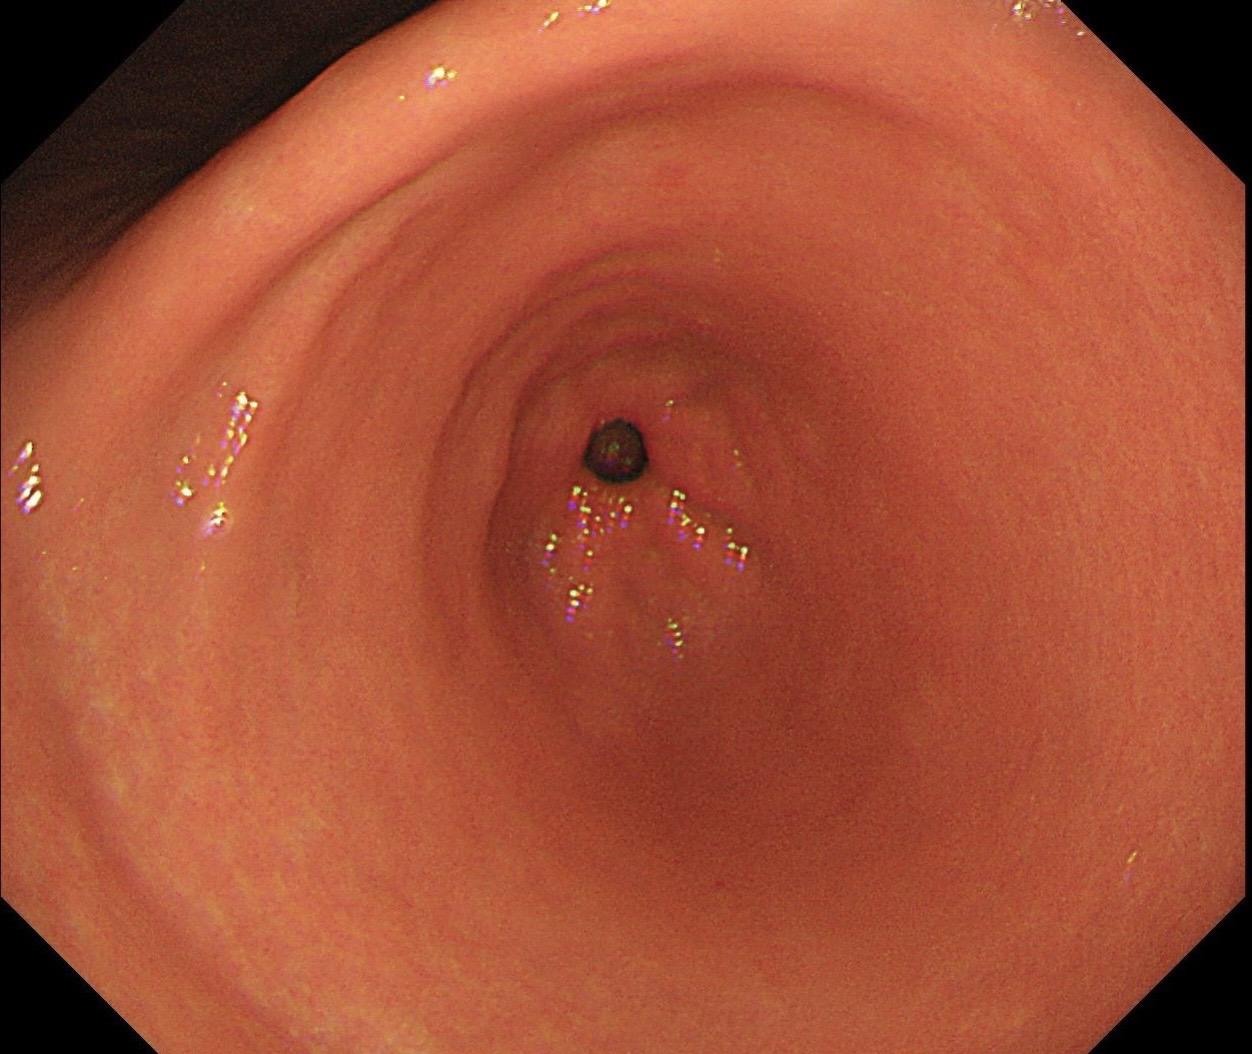

女,73岁,食管双发病变。泰州人,入院系统体检,首次胃镜检查,上段16...

男,40岁,胃双发褪色调病变。慢性胃炎复查,3年前胃镜未见异常,Hp阳...